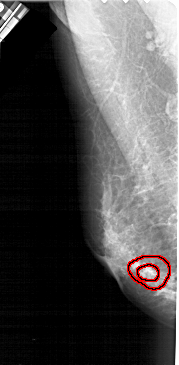

FILE: A_1938_1.LEFT_CC.OVERLAY

TOTAL_ABNORMALITIES 1

ABNORMALITY 1

LESION_TYPE MASS SHAPE IRREGULAR MARGINS SPICULATED

ASSESSMENT 5

SUBTLETY 2

PATHOLOGY BENIGN

TOTAL_OUTLINES 2